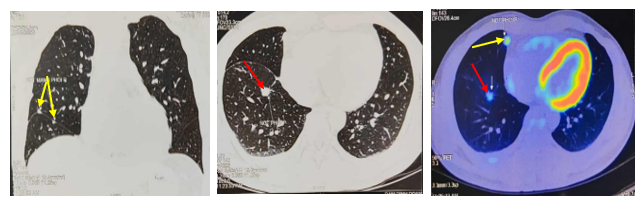

Bệnh nhân được chụp PET/CT tại Bệnh viện Vinmec cho kết quả: Các nốt đặc rải rác thùy giữa và dưới phổi phải, các nốt lớn tăng chuyển hoá FDG (suvmax 3,6), ít dịch màng phổi dày 9mm, nhiều nốt rải rác màng phổi thành ngực, hạch nhóm 2R,4R/7 rốn phổi phải, hạch lớn KT 17x10mm.

Hình 3: Hình ảnh chụp PET/CT các nốt tổn thương u tại phổi phải (mũi tên đỏ), nốt di căn màng phổi phải (mũi tên vàng)

Hình 4: Hình ảnh chụp PET/CT: Hạch trung thất, dịch màng phổi phải (mũi tên chỉ)